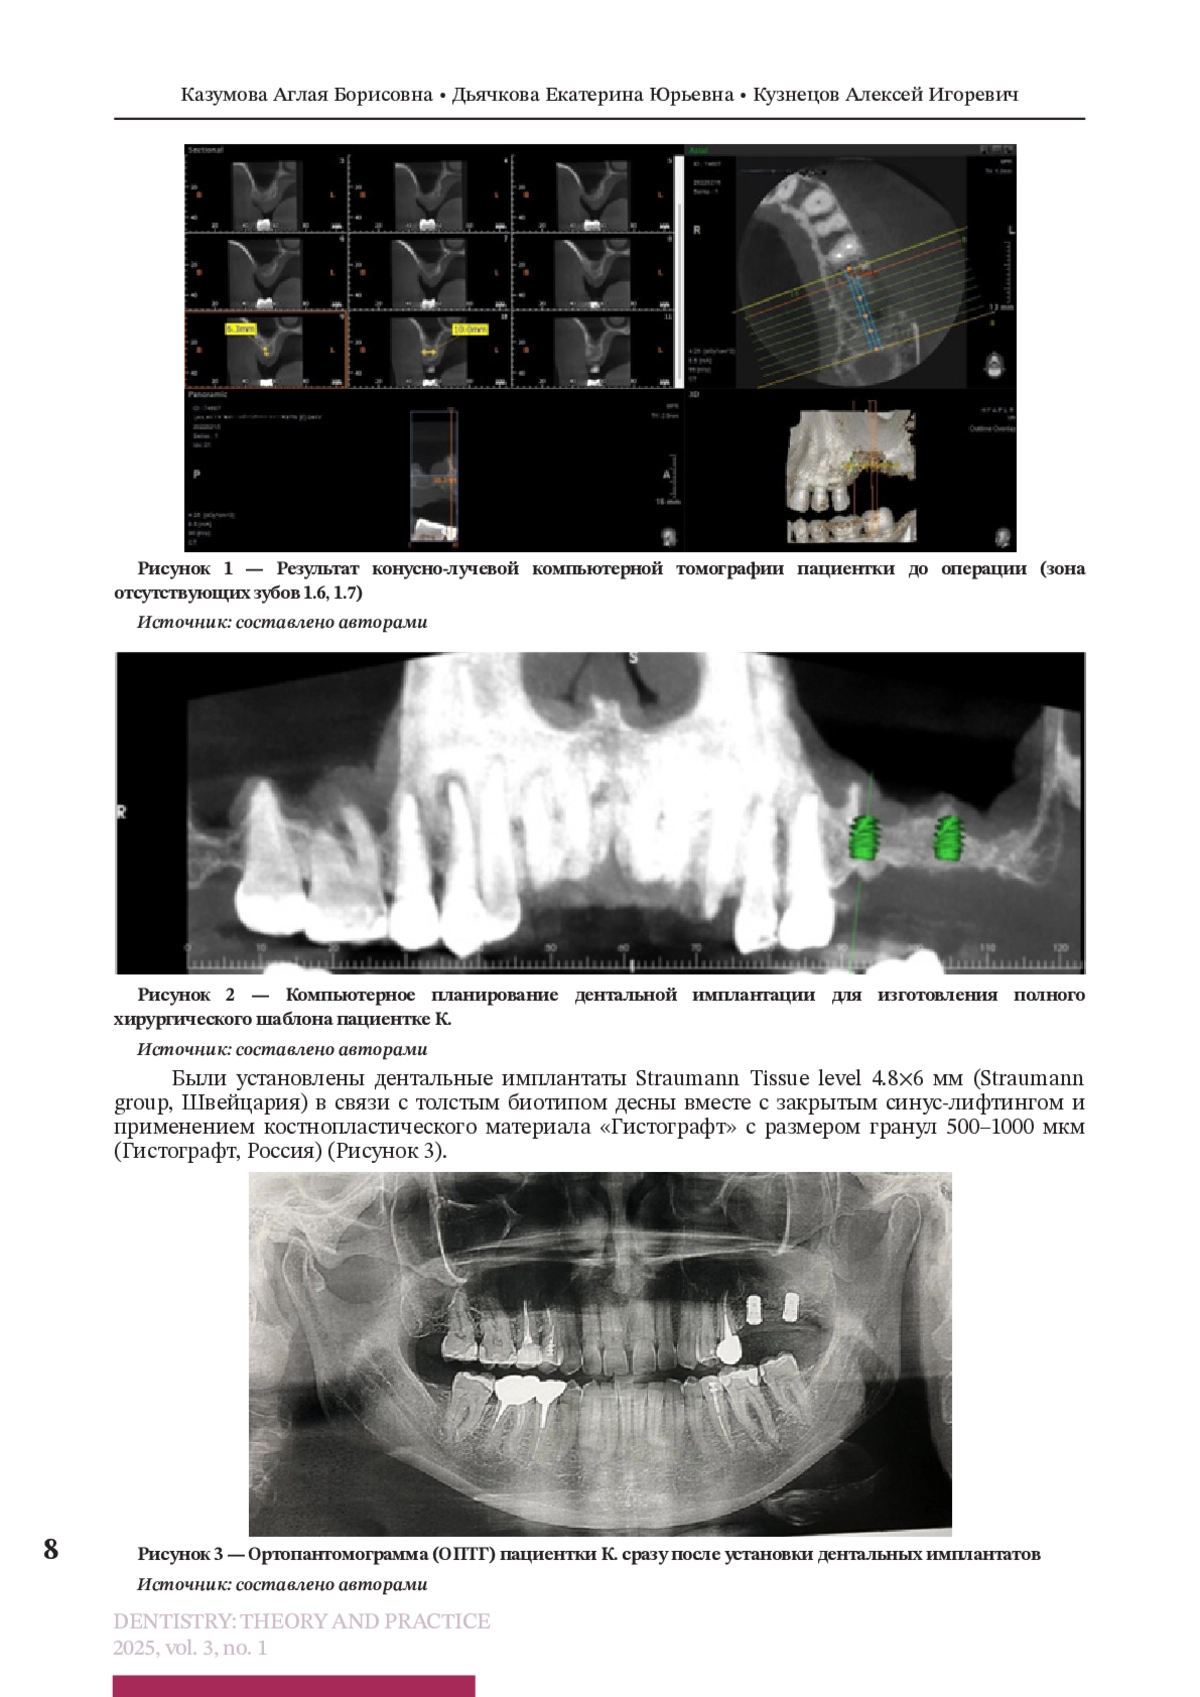

Регулирование витамином D метаболизма фосфата кальция и ремоделирования костей, а также противовоспалительные и иммуномодулирующие эффекты, регуляция пролиферации и дифференцировки клеток могут существенно повлиять на здоровье полости рта. Ряд клинических исследований и научных экспериментов продемонстрировал связь между низким уровнем витамина D и течением, и частотой рецидивирующего афтозного стоматита, ответом на лечение плоскоклеточного рака полости рта, тяжестью заболеваний пародонта, процессами остеоинтеграции и ремоделирования кости после дентальной имплантации и направленной костной регенерации. В данной статье мы приводим описание клинического случая протезирования с опорой на дентальные имплантаты у пациентки при выявленном дефиците витамина D3. Одним из основных этапов лечения являлось предоперационное обследование, включавшее оценку гормонального статуса и минерального обмена, в том числе — витамина D, паратгормона и маркеров остеогенеза, совместную работу с врачом-эндокринологом, назначение индивидуальной дозы витамина D для достижения референсных значений в сыворотке крови и дальнейшей поддерживающей дозы, что позволило достичь хорошей остеоинтеграции дентальных имплантатов и провести своевременное протезирование пациентки.